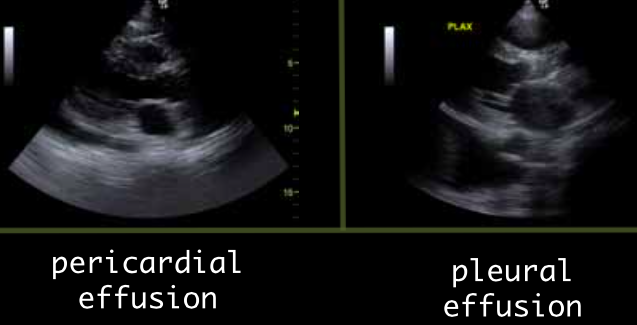

How do differentiate a pleural effusion from a pericardial effusion

Pericardial effusion has “rat tail” that goes between the heart and descending aorta. The pleural effusion goes behind the aorta.